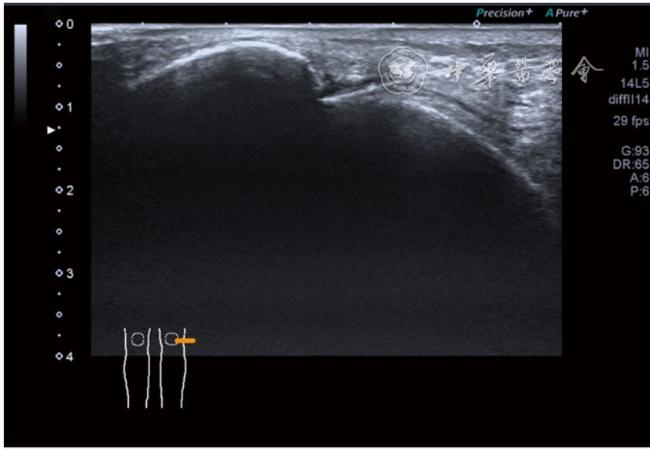

(五)超声影像学表现

患者采取侧卧位,患肢在上,屈膝20°。应用10~18 MHz高频线阵探头,扫查深度1~3 mm。长轴和短轴结合双侧对比扫查。超声影像学所见:短轴可见卡压腓总神经近端增粗,面积增大;长轴可见腓总神经卡压处变细,其近侧肿胀、回声减低,而在卡压远侧则表现正常(图35);一些受压严重者可以出现神经周围积液,卡压神经部位的筋膜增厚(图36);受压神经内血流增加对临床诊断意义更大(图37);探头在病变神经处加压常可引起神经刺激症状。腓总神经支配的肌肉有失神经支配改变,表现为肌肉回声增高和肌肉萎缩(图38)。

图35 超声短轴可见卡压腓总神经近端增粗,面积增大;长轴可见腓总神经卡压处变细,其近侧肿胀、回声减低